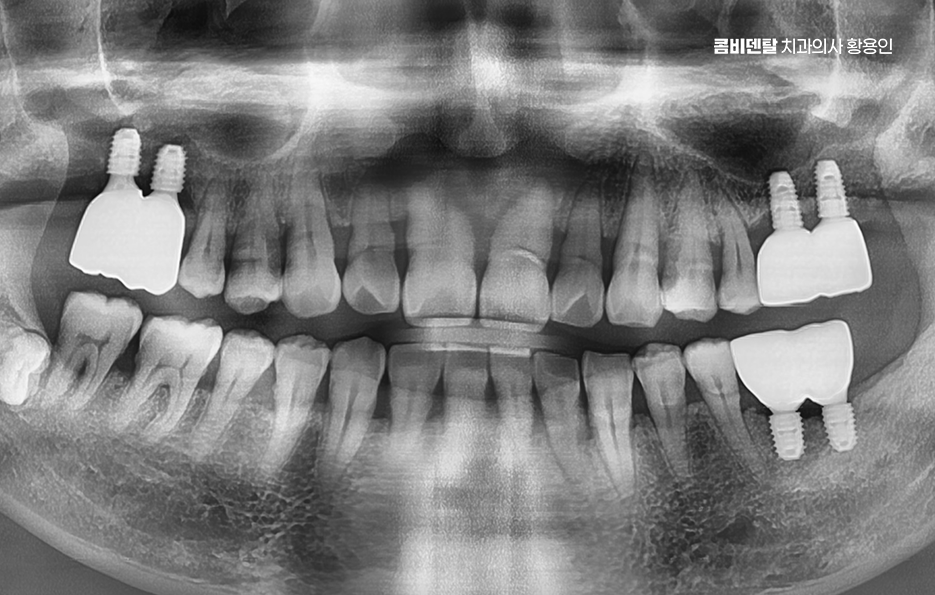

현재 기준으로 보면, 65세 이상이라면 평생 최대 2개까지 건강보험 적용으로 임플란트 치료를 받을 수 있으며 건강보험 자격에 따라 본인부담금이 다르긴 한데요, 일반 건강보험 가입자라면 본인부담금 30% , 차상위나 기초수급자라면 본인부담금 10~20% 수준까지도 혜택을 받을 수 있어요.

정리하자면, 고령층에서 임플란트는 단순한 치료가 아니라 건강한 노년기 삶을 위해서도 중요하다는 점과 어르신 임플란트 지원을 통해서 평생 2개 까지 건강보험 혜택이 적용 가능하다는 이점과 더불어서 고령층에게 적용되는 혜택인 만큼 치료의 준비부터 사후관리까지 종합적으로 고려하여 치료 계획을 철저히 세워보시길 바라고 있었어요